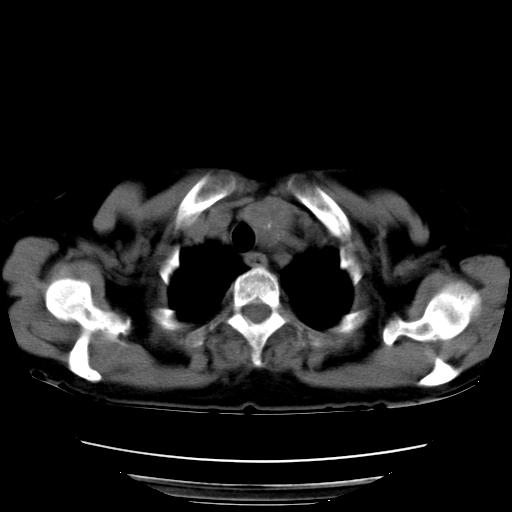

以下是引用夏季在2007-9-18 11:00:00的发言:[br]1。右肺肿块,周围有短毛刺,肺门侧有血管与其相连,胸壁侧有胸膜凹陷征,考虑周围性肺癌 2。左侧甲状腺软组织肿块,内有高密度钙化灶,考虑左侧甲状腺腺瘤。

以下是引用卜一在2007-9-18 14:41:00的发言:[br]右肺肿块:毛刺+胸膜凹陷征+供血血管+浅分叶+强化。支持:周围性肺癌 !另:左侧甲状腺腺瘤!